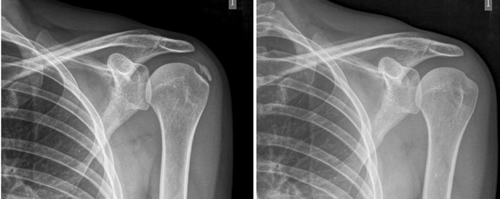

Figura 1